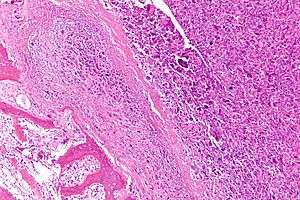

| Intermediate-magnification micrograph of an osteosarcoma (center and right of image) adjacent to non-malignant bone (left-bottom of image): The top-right of the image has poorly differentiated tumor. Osteoid with a high density of malignant cells is seen between the non-malignant bone and poorly differentiated tumor (H&E stain). | |

Microscopically: The characteristic feature of osteosarcoma is presence of osteoid (bone formation) within the tumor. Tumor cells are very pleomorphic (anaplastic), some are giant, numerous atypical mitoses. These cells produce osteoid describing irregular trabeculae (amorphous, eosinophilic/pink) with or without central calcification (hematoxylinophilic/blue, granular)—tumor bone. Tumor cells are included in the osteoid matrix. Depending on the features of the tumor cells present (whether they resemble bone cells, cartilage cells, or fibroblast cells), the tumor can be subclassified. Osteosarcomas may exhibit multinucleated osteoclast-like giant cells.[18]